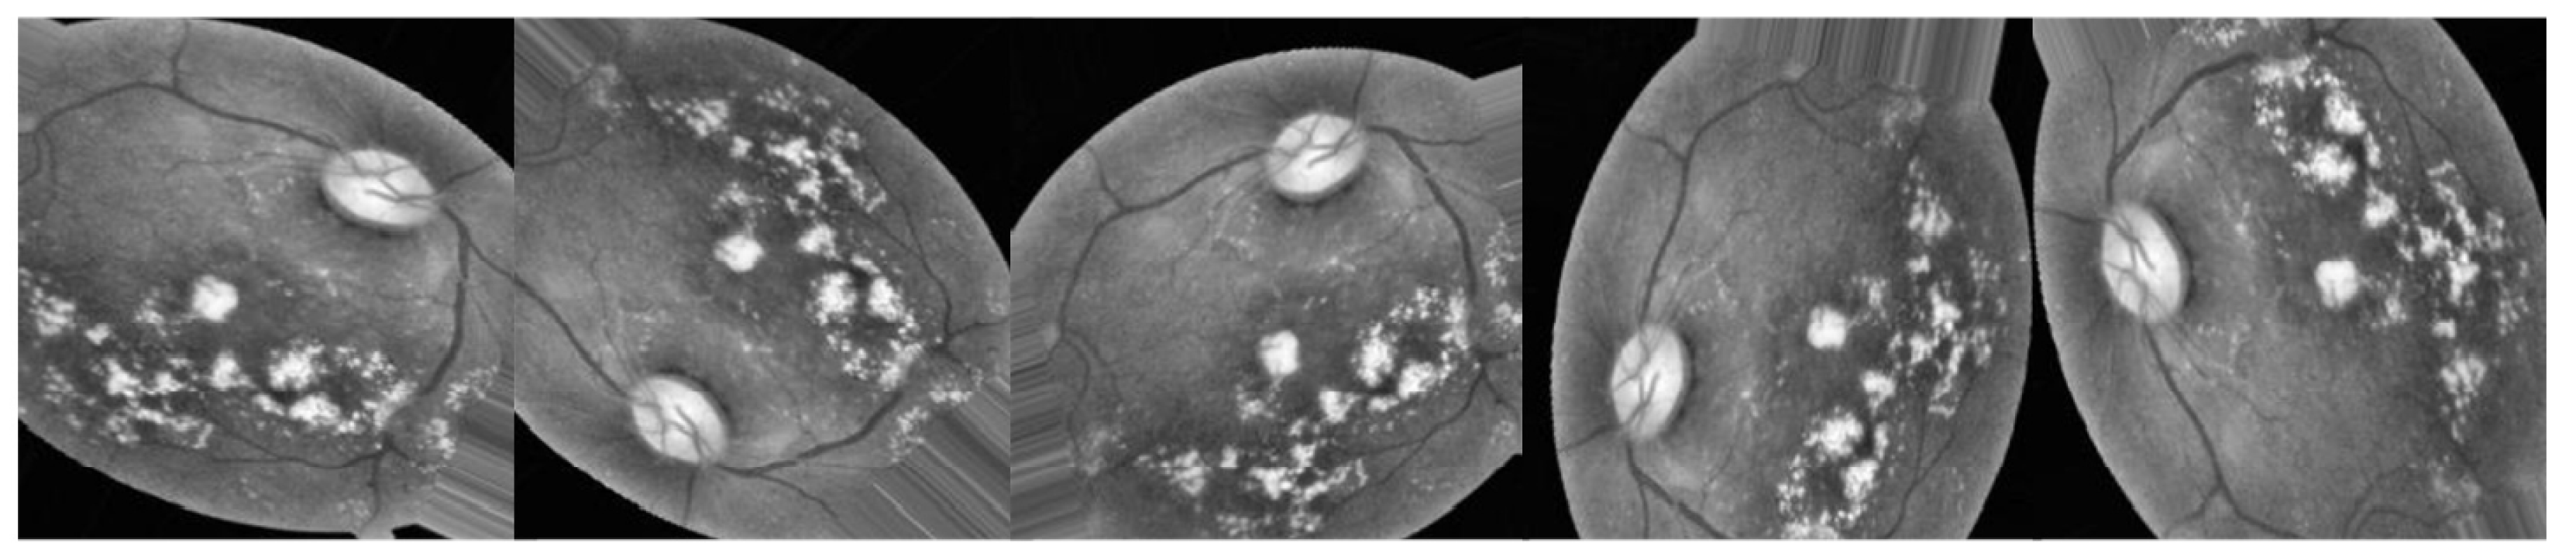

3.2.1. Preprocessing Using CLAHE and ESRGAN

- CLAHE

- ESRGAN

- Normalization